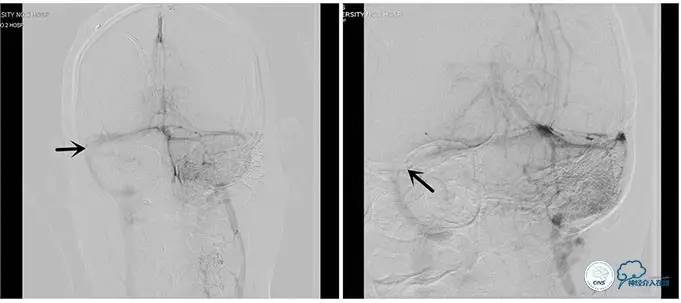

术后右侧ICA造影

术后远、近端压力差为:0

术后右侧ICA斜位

结果

术后即刻患者诉头痛完全缓解。

双眼视力较前有改善。

3天后腰穿:颅内压:75mmH2O,转当地医院眼科继续治疗。